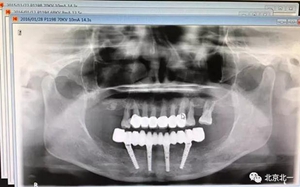

圖一:術(shù)前CBCT

圖十五:術(shù)后即刻拍X片

圖二十一:半年后復(fù)查X片

圖二十二:2015年到2016年復(fù)查時(shí)X片 ,有圖有真相